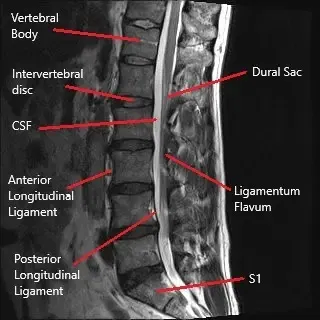

Sagittal section of the lumbar MRI.

The lumbar spine consists of five vertebrae (L1-L5) separated by intervertebral discs. These discs act as cushions to absorb shock and allow movement. The spinal cord passes through the central canal, and nerve roots branch out from the spinal cord, exiting the spinal column through the intervertebral foramen. These nerves control sensation and movement in the lower body. A herniated disc can compress these nerve roots, leading to symptoms such as pain, tingling, and weakness.

MRI (Magnetic Resonance Imaging): The most effective tool for visualizing soft tissues like discs and nerve roots. It can confirm disc herniation and nerve compression.